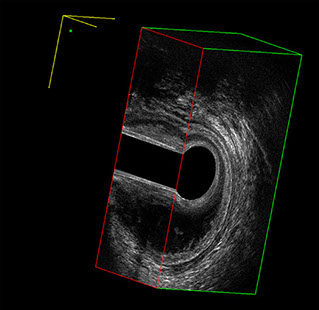

L’ecografia transanale è un esame diagnostico per immagini che consiste nell’introduzione di un trasduttore ad ultrasuoni. Le immagini qualitativamente migliori del canale anale sono ottenute usando un trasduttore rotante, montato in un manipolo rigido, che fornisce un’immagine a 360°. Con le apparecchiature più moderne è anche possibile ottenere immagini tridimensionali.

Proctal dispone di apparecchiatura per ecografia endoanale 3D con sonda rotante.